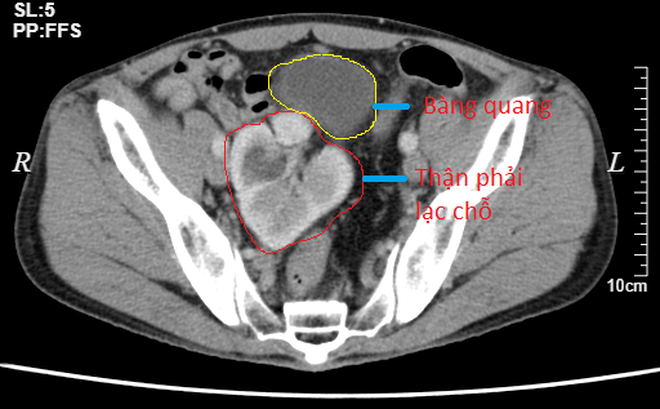

Sau nhập viện, bệnh nhân được chỉ định làm các cận lâm sàng cần thiết, kết quả chụp CT đa dãy cho thấy hình ảnh nang nhỏ thận phải, thận phải lạc chỗ trong tiểu khung lệch phải kích thước bình thường, nhu mổ có nang nhỏ 17mm.

Qua các kết quả cận lâm sàng các bác sỹ chẩn đoán bệnh nhân bị nang thận phải, thận phải lạc chỗ và cần phẫu thuật cố định thận phải.